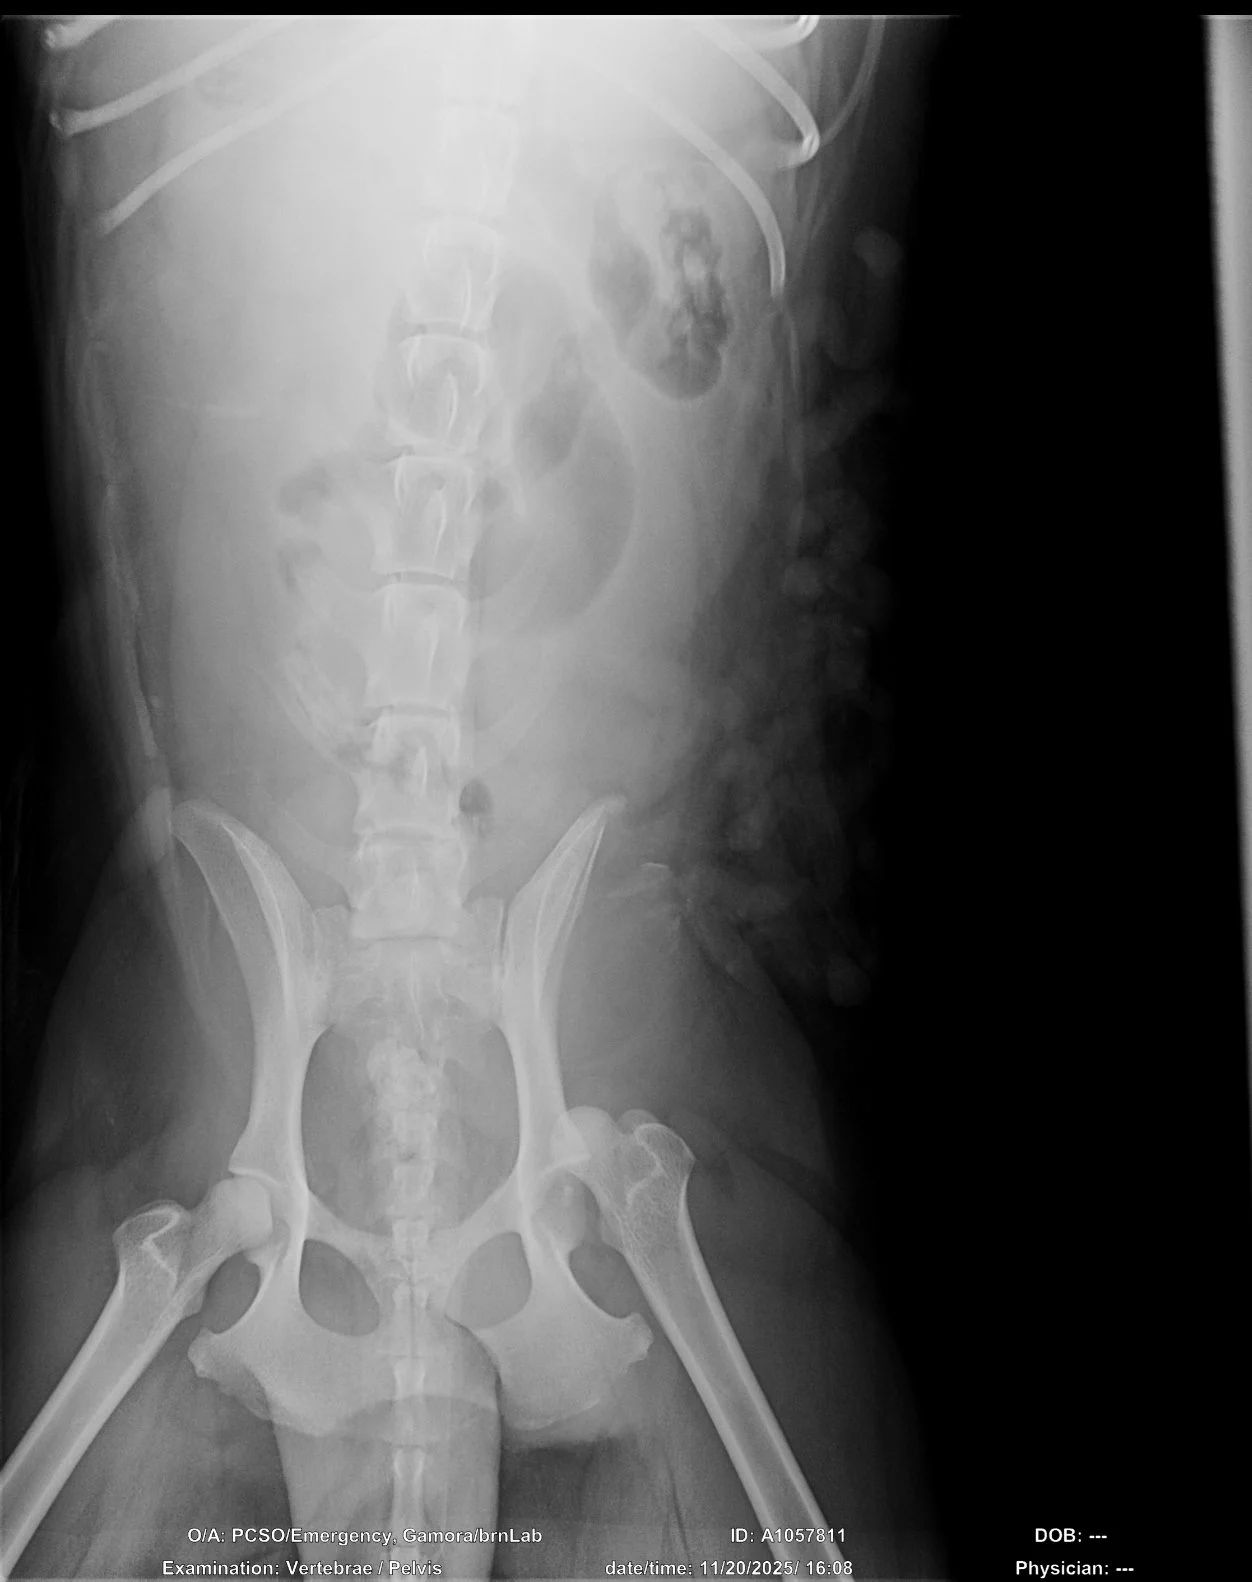

Frankie’s Friends’ Vet Care for Rescues Grant Program helped Gamora receive surgery for a luxated femur after being hit by a car.

Gamora was found laying on the side of the road after being hit by a car. Thank you for helping us give Gamora the chance she deserves.